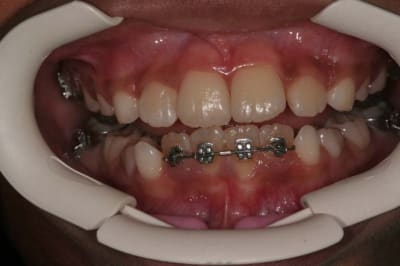

Img 1 xacnga - Eugenol

Img 2 siytdm - Eugenol

Img 3 ituagt - Eugenol

Img 4 r3tw6u - Eugenol

Img 5 z8ak0k - Eugenol